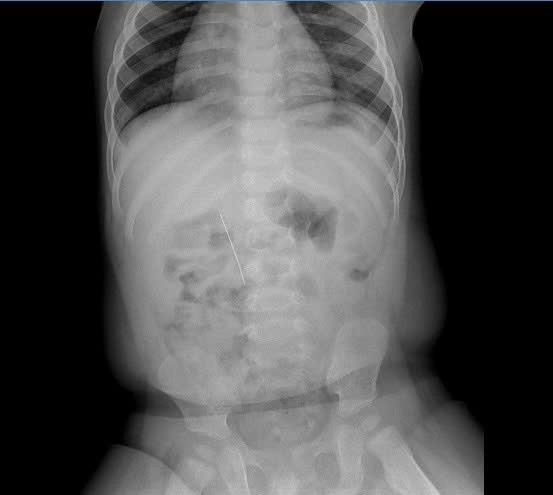

Hình ảnh chụp X-quang cho thấy dị vật nằm trong ổ bụng rất rõ - Ảnh BVCC

Kết quả chụp X-quang ổ bụng không chuẩn bị ghi nhận có hình ảnh là dị vật cản quang thẳng, dài, nằm ở vị trí tương ứng các đốt sống L1–L3, phù hợp với dị vật kim may nằm trong đường tiêu hóa. Trẻ được chẩn đoán Dị vật đường tiêu hóa (mã bệnh T18) và chỉ định nhập viện vào khoa Tiêu hóa để theo dõi, hội chẩn và xử trí cấp cứu.